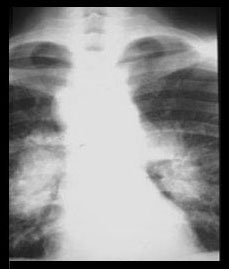

STAGE I STAGE II

Thoracic lymphadenopathy. Normal lung parenchyma. ( 50% )